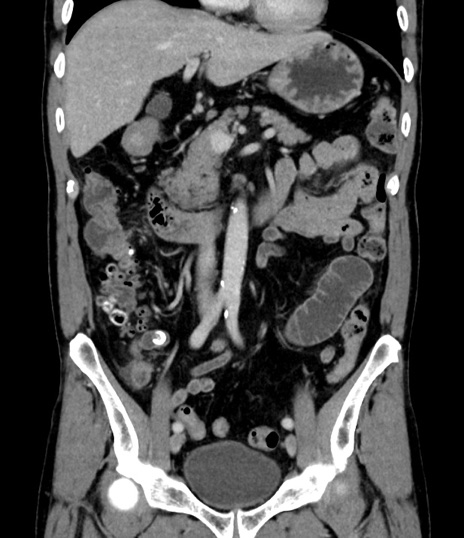

症例8(冠状断像)

【症例】 60歳代男性

【主訴】 黒色吐物

【現病歴】 4日前から嘔気自覚、2日前の朝食後にも嘔気あり、自分で手で嘔吐反射起こし嘔吐したところ血が混ざっていたため受診。

【既往歴】 5年前汎発性腹膜炎を伴う急性虫垂炎で手術、高血圧、前立腺肥大症、高脂血症

【身体所見】 腹部正中に手術癩痕あり 腹部平坦・軟圧痛なし膨満感あり

【データ】WBC 8400、CRP 4.54

横断像